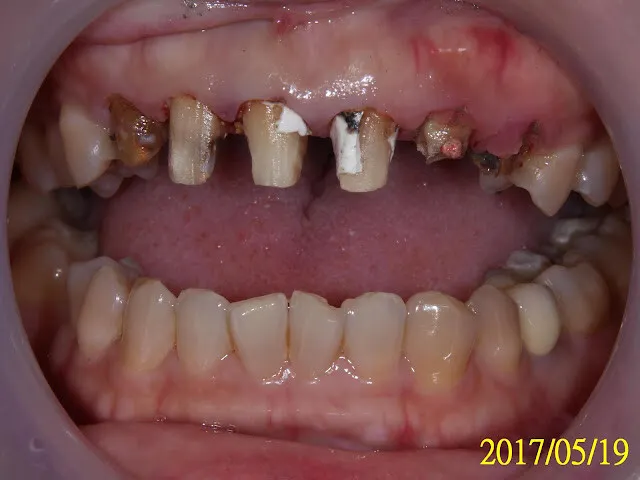

有圖有真相,令人震驚與難過的真相,這就是我常說的一翻兩瞪眼,像在『拆禮物』,沒拆開前永遠不知道真相左上爛牙齦發炎知道原因了,原來是爛到斷頭的牙根,之後還要先修牙齦(下詳)

白白的是原來假牙的殘餘的黏著劑,我都還沒清掉就先照相,第一現場記錄。黑黑的是蛀牙。

粉紅色是根管治療(抽神經)的封填材料,一般是包在齒質內的,看不到的,現在像裸露的鋼筋,暴露在外,因為包裹的齒質已蛀到斷頭。

先從右邊的支台齒(牙套下面的牙齒,被車過的,醫學專與名詞是abuntment tooth,支台齒)說起,按順序,從右到左(圖片的方向是跟您相反的喔,鏡相)。

那顆犬齒(虎牙)都被蛀到整顆牙齒變顏色了(原來的顏色應該像他隔壁的鄰居支台齒),臨床代表意義快要牙髓神經發炎了,火山要爆發了(就是會讓你徹夜難眠的牙痛的比喻)。還好她當時並不會痛,無症狀,我試著移除蛀牙光補蛀牙,看能不能救回這顆牙齒(算是另類的活髓治療)。結果在下方的圖片,有圖為證。要花多久?半年以上,圖片有日期。

可以看到左邊的側門牙與虎牙,都已蛀到斷頭,牙齦還增生包住了,之前做假牙時絕對不是這樣,會是像隔壁的支台齒。